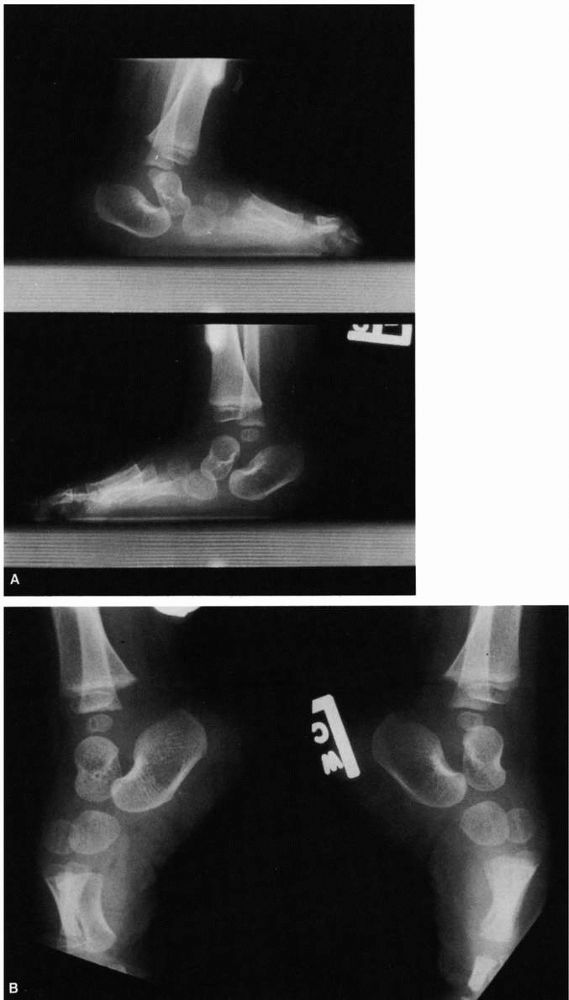

![]() |

FIGURE 20-12.

Congenital vertical talus. Newborn with sacral agenesis and bilateral congenital vertical talus. The heels are in valgus and the forefoot is abducted. The foot has the characteristic rocker-bottom deformity. |

FIGURE 20-13.

Congenital vertical talus of left foot. (Hypermobile flatfoot with contracted Achilles tendon on the right foot.) In the simulated weight-bearing views (upper left and upper right), both feet have the evidence of a rocker-bottom deformity with dorsiflexion occurring at the midfoot, the hindfoot is in equinus, and the forefoot is in dorsiflexion. The talus is more severely plantar flexed on the left than the right. Both calcanea are in equinus, and on the left foot there is disruption of the calcaneal cuboid joint. On the plantar flexion views (bottom), note on the right side the longitudinal axis of the talus is collinear with the forefoot; but on the left (side with congenital vertical talus), the longitudinal axis of the talus is not collinear with the longitudinal axis of the metatarsals, indicative of the rigid nature of the deformity. |